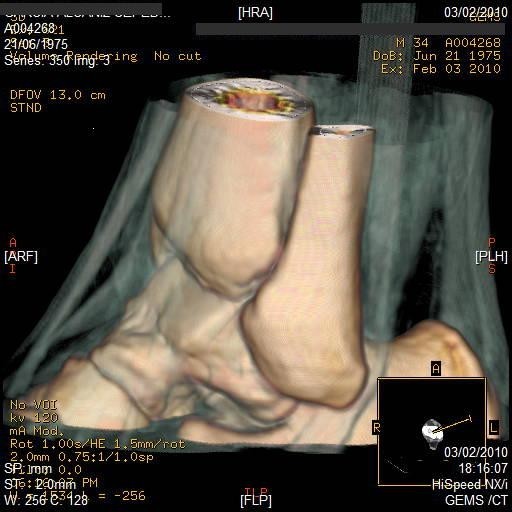

Tomografía Computada: Imágenes Superiores a los Rayos X

La tomografía computada (CT) combina la ciencia de los rayos X con la tecnología computarizada para producir imágenes más enfocadas e informativas que los rayos X tradicionales. Las tomografías computadas producen imágenes claras de los huesos, tejidos blandos, órganos, discos intervertebrales y médula espinal. Las imágenes pueden reproducirse en tonos de negro/gris/blanco o en color. Para mejorar la imagen puede inyectarse al paciente un medio de contraste (tinción) durante la prueba.

Durante una tomografía, una serie de rayos X se dirigen en ángulos específicos para atravesar la parte del cuerpo que se está examinando. Un detector del lado opuesto transmite los detalles de la exploración a una computadora, la cual analiza la información y produce imágenes transversales de esa parte del cuerpo. Las imágenes transversales o “rebanadas” se conocen como tomogramas. Las imágenes pueden mostrarse en un monitor, guardarse como archivos en la computadora, o imprimirse en película común de rayos X.